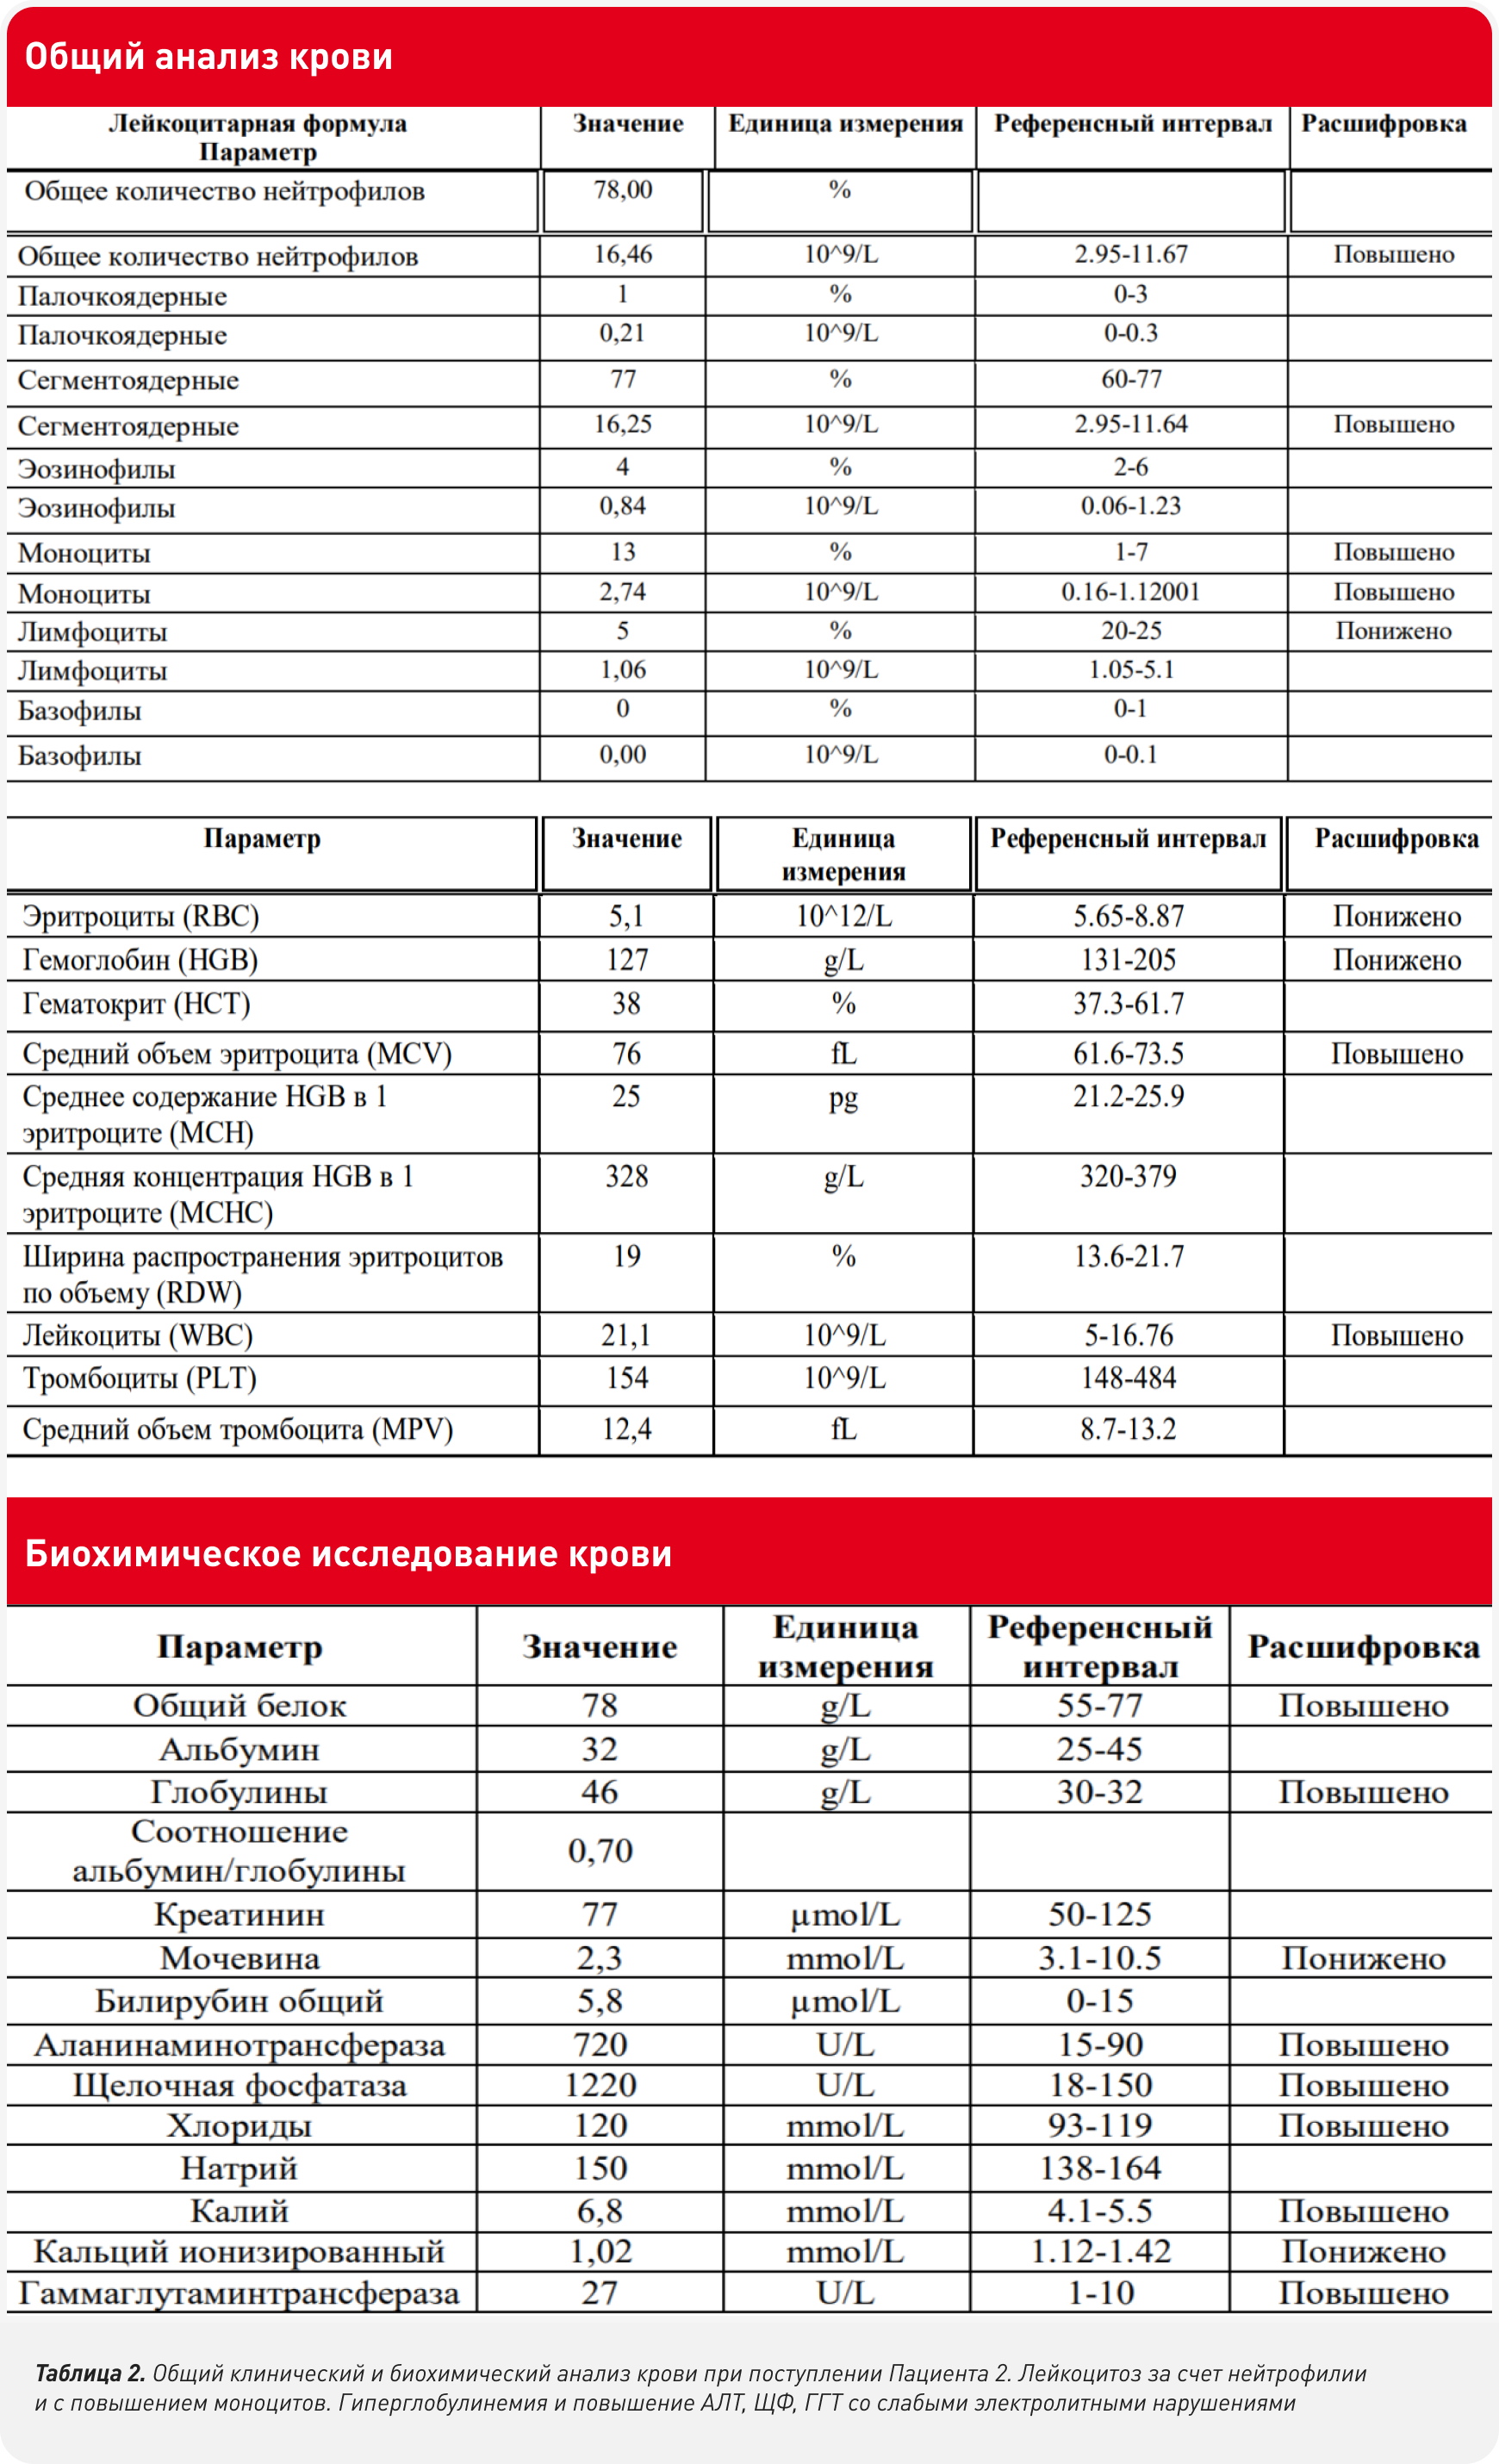

Оба пациента были отправлены на УЗИ (рис.1-2 соответственно) для дальнейшей диагностики лейкоцитоза и повышения ферментов.

Оба пациента через 7 дней после операции были выписаны на консервативное лечение с рекомендацией повторного приема гастроэнтеролога для оценки динамики. На повторном приеме выявлены жалобы о эпизодических болевых синдромах, которые купировались приемом анальгезирующих препаратов, у Пациента 2 была отмечена однократная рвота и однократный отказ от еды, который купировался самостоятельно. Оценка биохимического анализа крови выявило значимое снижение щелочной фосфатазы и АЛТ, что было расценено как положительная динамика (Таб 3.)

Исходя из представленных клинических случаев общими симптомами некротизирующего холецистита были абдоминальная боль, гипорексия, летаргия, а также, возможно, мелена, что не является типичным симптомом. Несмотря на подтвержденный некроз стенки желчного пузыря и холестаз ни у одного пациента не было выявлено гипербилирубинемии и как следствие желтушных слизистых. Также не наблюдался и лейкоцитоз с повышением юных форм нейтрофилов в крови.

Общими отклонениями в анализе крови являлись: лейкоцитоз с повышением моноцитов, гиперглобулинемия, повышение АЛТ, ЩФ, ГГТ. На ультразвуковом исследовании желчный пузырь имел: сильное наполнение, округлую форму, выраженную слоистость стенок с нарушением дифференциации от содержимого, гетерогенные структуры в просвете (вероятно, представленные сгустками или холелитами), а также локальный стеатит с затуханием эхо-сигнала и свободную жидкость, что указывало на остроту процесса.